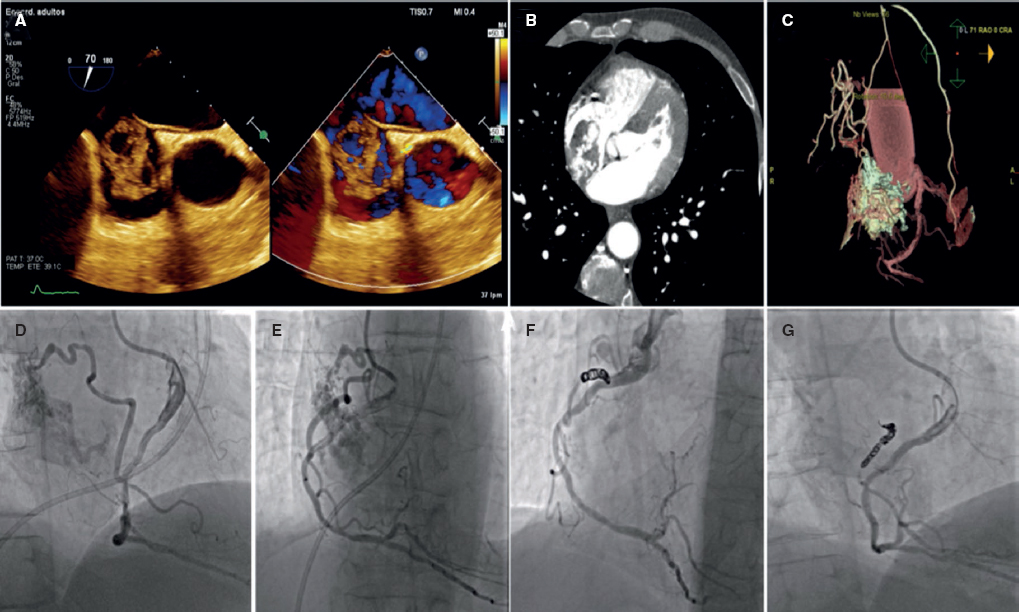

Lactante de 2 meses recientemente intervenido de cierre de comunicación interventricular perimembranosa con clínica congestiva en el posoperatorio y sospecha ecocardiográfica de posible fístula de coronaria derecha a ventrículo derecho, confirmada con la realización de una tomografía computarizada cardiaca y un cateterismo con coronariografía no selectiva. Se obtuvo el consentimiento informado de los padres para la difusión del caso. Se observa una gran fístula coronaria desde la rama marginal de la coronaria derecha desembocando en la cavidad del ventrículo derecho con gran dilatación del segmento proximal de la coronaria derecha (figura 1) favorable para cierre percutáneo. Con un catéter transportador de 4 Fr sondando la coronaria derecha se avanza una guía coronaria hasta el ventrículo derecho y, asistido por balón de angioplastia, se avanza el catéter transportador hasta la zona proximal de la fístula, donde se libera un dispositivo Amplatzer Vascular Plug (AVP4) (Abbott, USA) 4 × 6, con oclusión completa del defecto sin interferencia con la coronaria derecha distal (figura 2).

Figura 2.